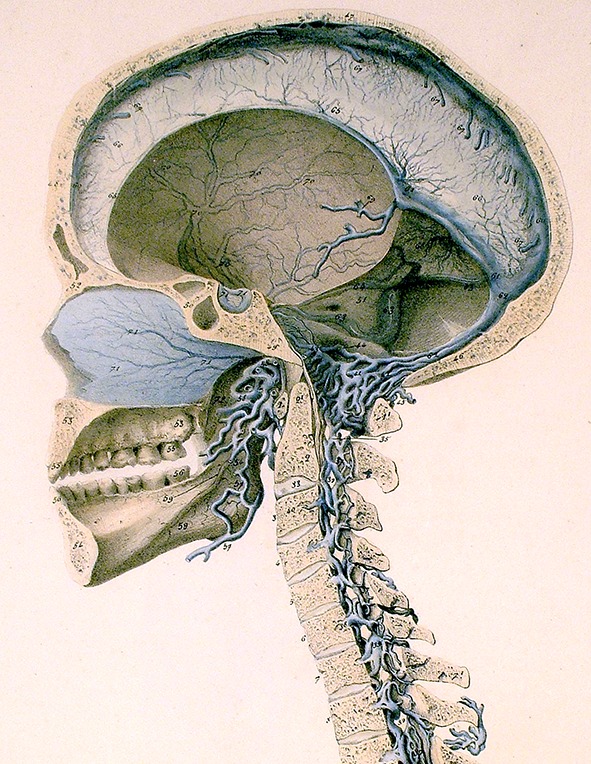

In contrast to its rapid brain effects when injected perispinally, etanercept has difficulty crossing the blood–brain barrier in therapeutic quantities when administered systemically [9, 11, 14, 16, 17]. To avoid the trauma associated with invasive methods of brain delivery, such as intracerebroventricular injection, a new method of drug delivery was needed to facilitate the use of etanercept for brain disorders [9, 11, 14–17]. Perispinal administration was designed as a novel method to enhance delivery of etanercept and other large molecules to the brain via the cerebrospinal venous system (CSVS) (Fig. 2) [6, 9, 11, 14–18].

Fig. 2.

Cerebrospinal venous system. Detail of plate 5 from Breschet [26].

Courtesy of the Sidney Tobinick collection, modified from the original

The CSVS consists of the interconnected cerebral and spinal venous systems, a unique, large capacity, essentially valveless venous network within which bi-directional blood flow occurs, including retrograde blood flow from the spinal venous blood into the brain [11, 16, 18]. Venous drainage of the anatomical region posterior to the spine is accomplished by the external vertebral venous plexus, the most superficial component of the CSVS [11, 16, 18]. The external vertebral venous plexus drains into the internal vertebral venous plexus, which itself drains, and drains into the cerebral venous system [11, 16, 18]. Perispinal injection of etanercept delivers etanercept into the catchment area of the external vertebral venous plexus, thereby enabling etanercept to bypass the blood–cerebrospinal fluid barrier and reach the brain [6–11, 13–19].